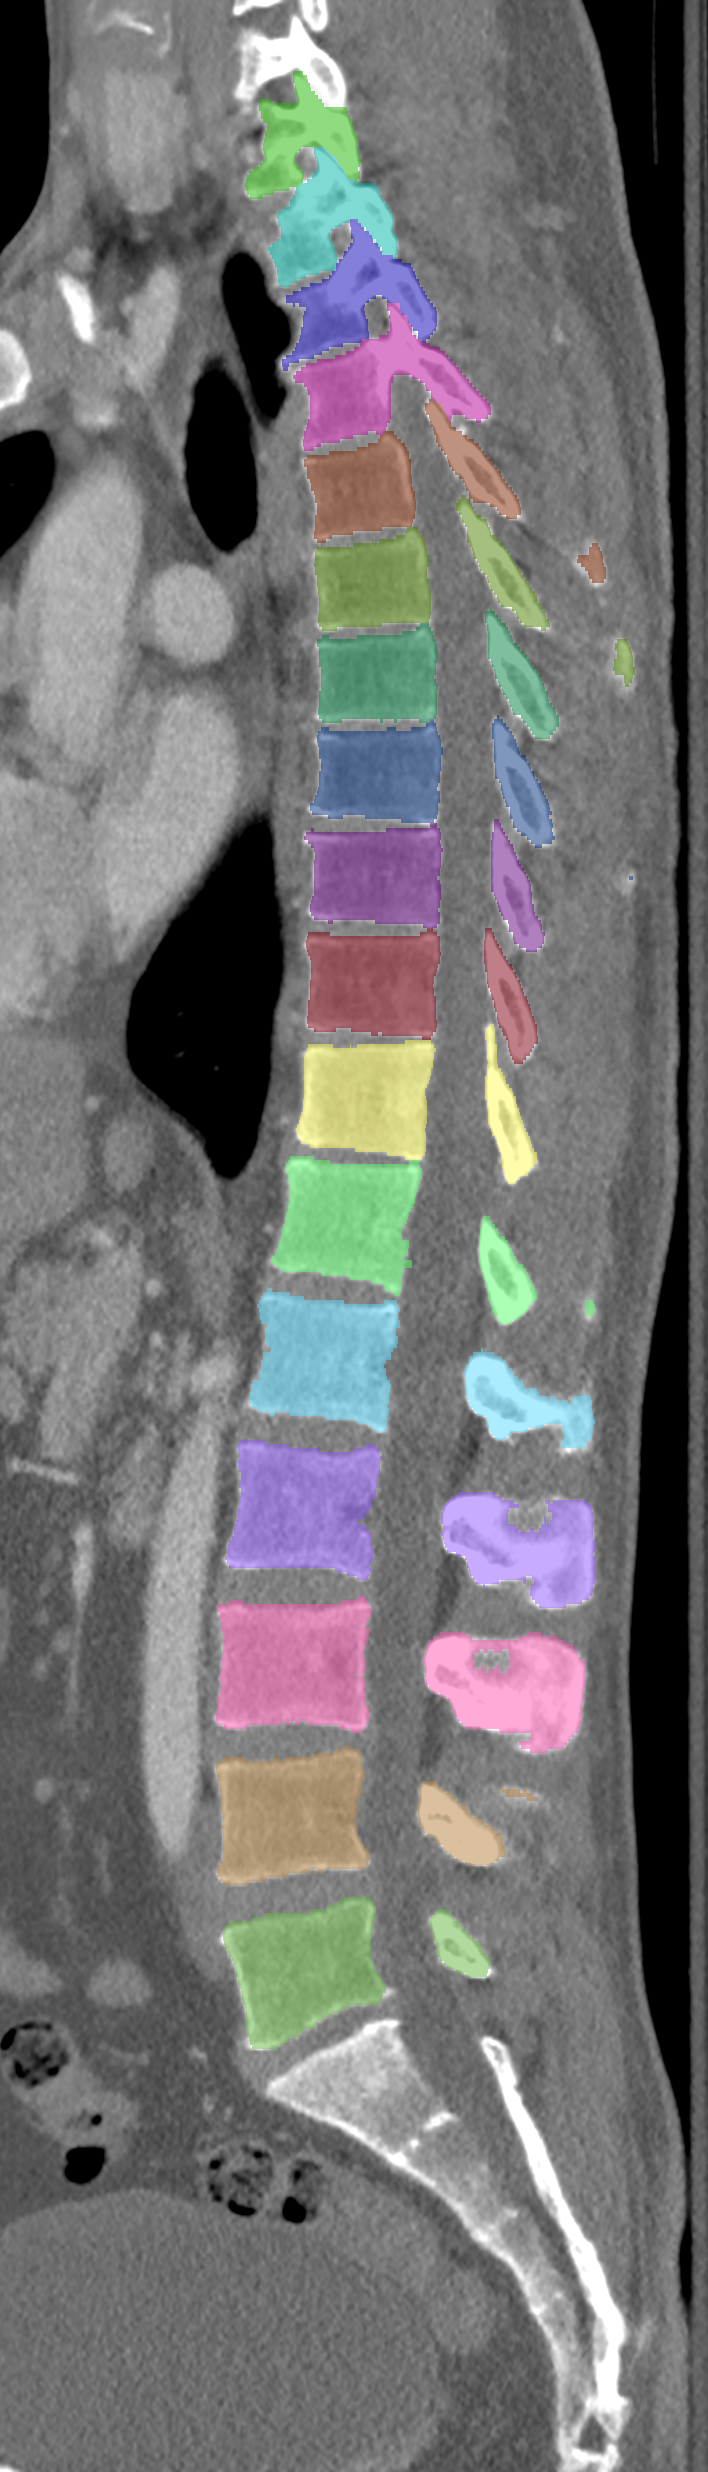

Normalized CT images and reference segmentations of thoracic and lumbar vertebrae from the CSI 2014 workshop

Description

This is the dataset of the vertebra segmentation challenge of the CSI 2014 workshop that was held in conjunction with MICCAI 2014.

- Vertebrae have been anatomically labeled (8 = T1, 9 = T2, ..., 24 = L5)

- Because not always all visible vertebrae were segmented in the original data, only segmentations of the thoracic and lumbar vertebrae have been retained